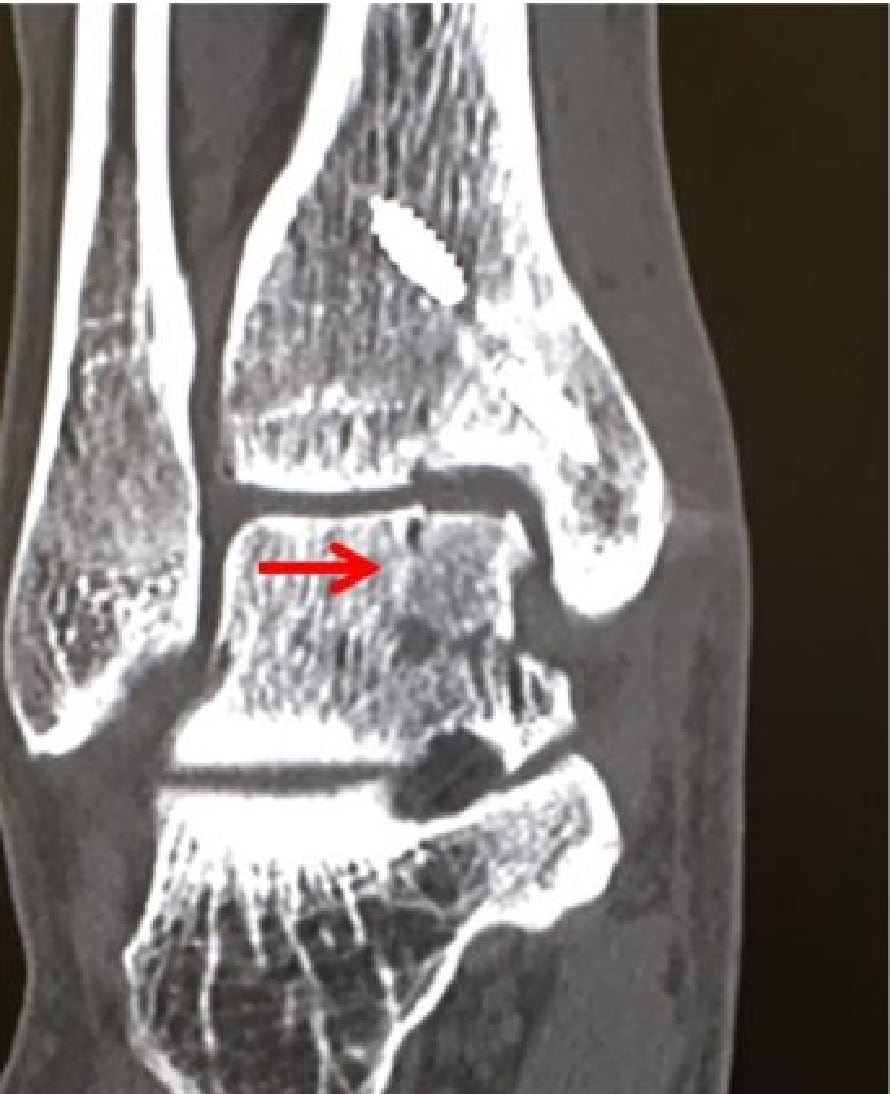

2020-12-09 スポーツ整形 ページ内リンク 距骨骨軟骨損傷(離断性骨軟骨炎)【スポーツ整形外科】 距骨骨軟骨損傷(離断性骨軟骨炎)【スポーツ整形外科】 軟骨とその下の骨が剥がれてきて痛みが出る。⇒骨穿孔/骨軟骨片固定/骨軟骨柱移植 患部の状態により最適な治療方法を選択します。 骨軟骨柱移植前 骨軟骨柱移植後 骨軟骨柱移植術後CT 関連ページ スポーツ整形 一覧へ戻る